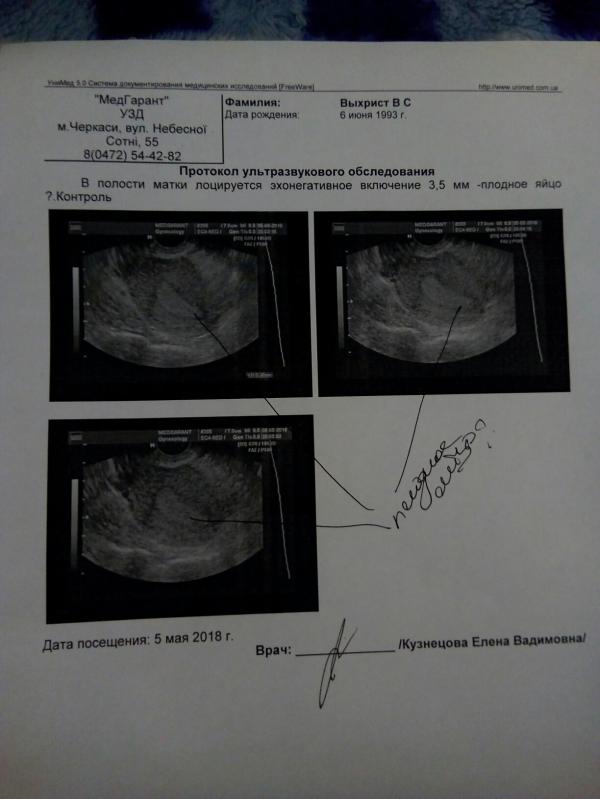

Доброй ночи, уснуть не могу мажет уже 2 день темно-коричневым. Сделала сегодня УЗД так как к врачу не попала, по скорой сказали что таким не занимаются в понедельник в ж/к... Приблизительно 6 неделя.